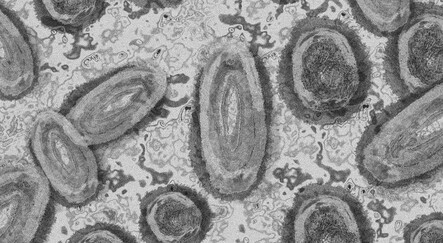

MAYMUN ÇİÇEĞİ VİRÜSÜ

Endemik bir virüsün neden olduğu nadir hastalıklardan maymun çiçeği, Kongo ve Batı Afrika türü olmak üzere 2'ye ayrılıyor.

Genellikle hayvandan insana ve nadiren insandan insana yakın temasla bulaşan virüs, vücutta yüksek ateş ve kaşıntılı kabarcıklara yol açabiliyor.